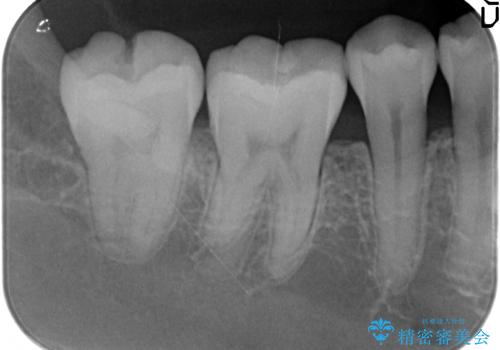

- 右下の奥歯が冷たいものがしみるので診て欲しいといらっしゃった方の症例です。

樹脂と虫歯を除去後、セラミックインレーによる修復を行いました。